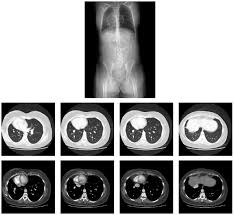

Para 2012, a expectativa é fortalecer ainda mais o relacionamento médico e ampliar a variedade de novos serviços. Ainda no próximo ano, o Exame passará a oferecer exames de imagem, tais como ressonância magnética, tomografia computadorizada, raio X, ultrassonografia e mamografia.